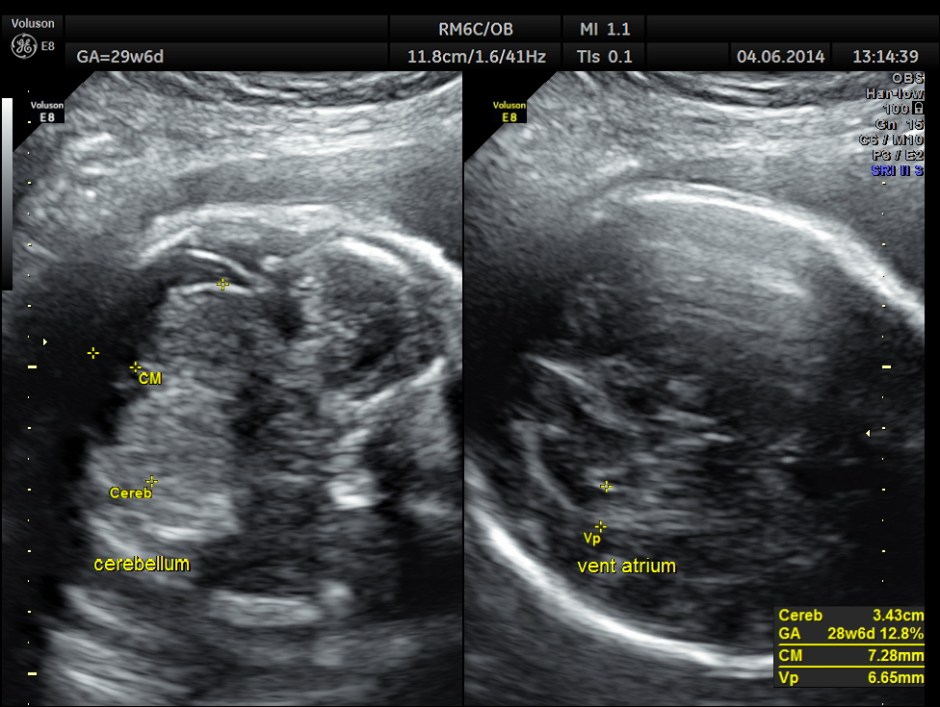

Biometric measurements show AC <2.3 %TILE

BPD , HC <10 % tile and AC is < 2.3 % tile .